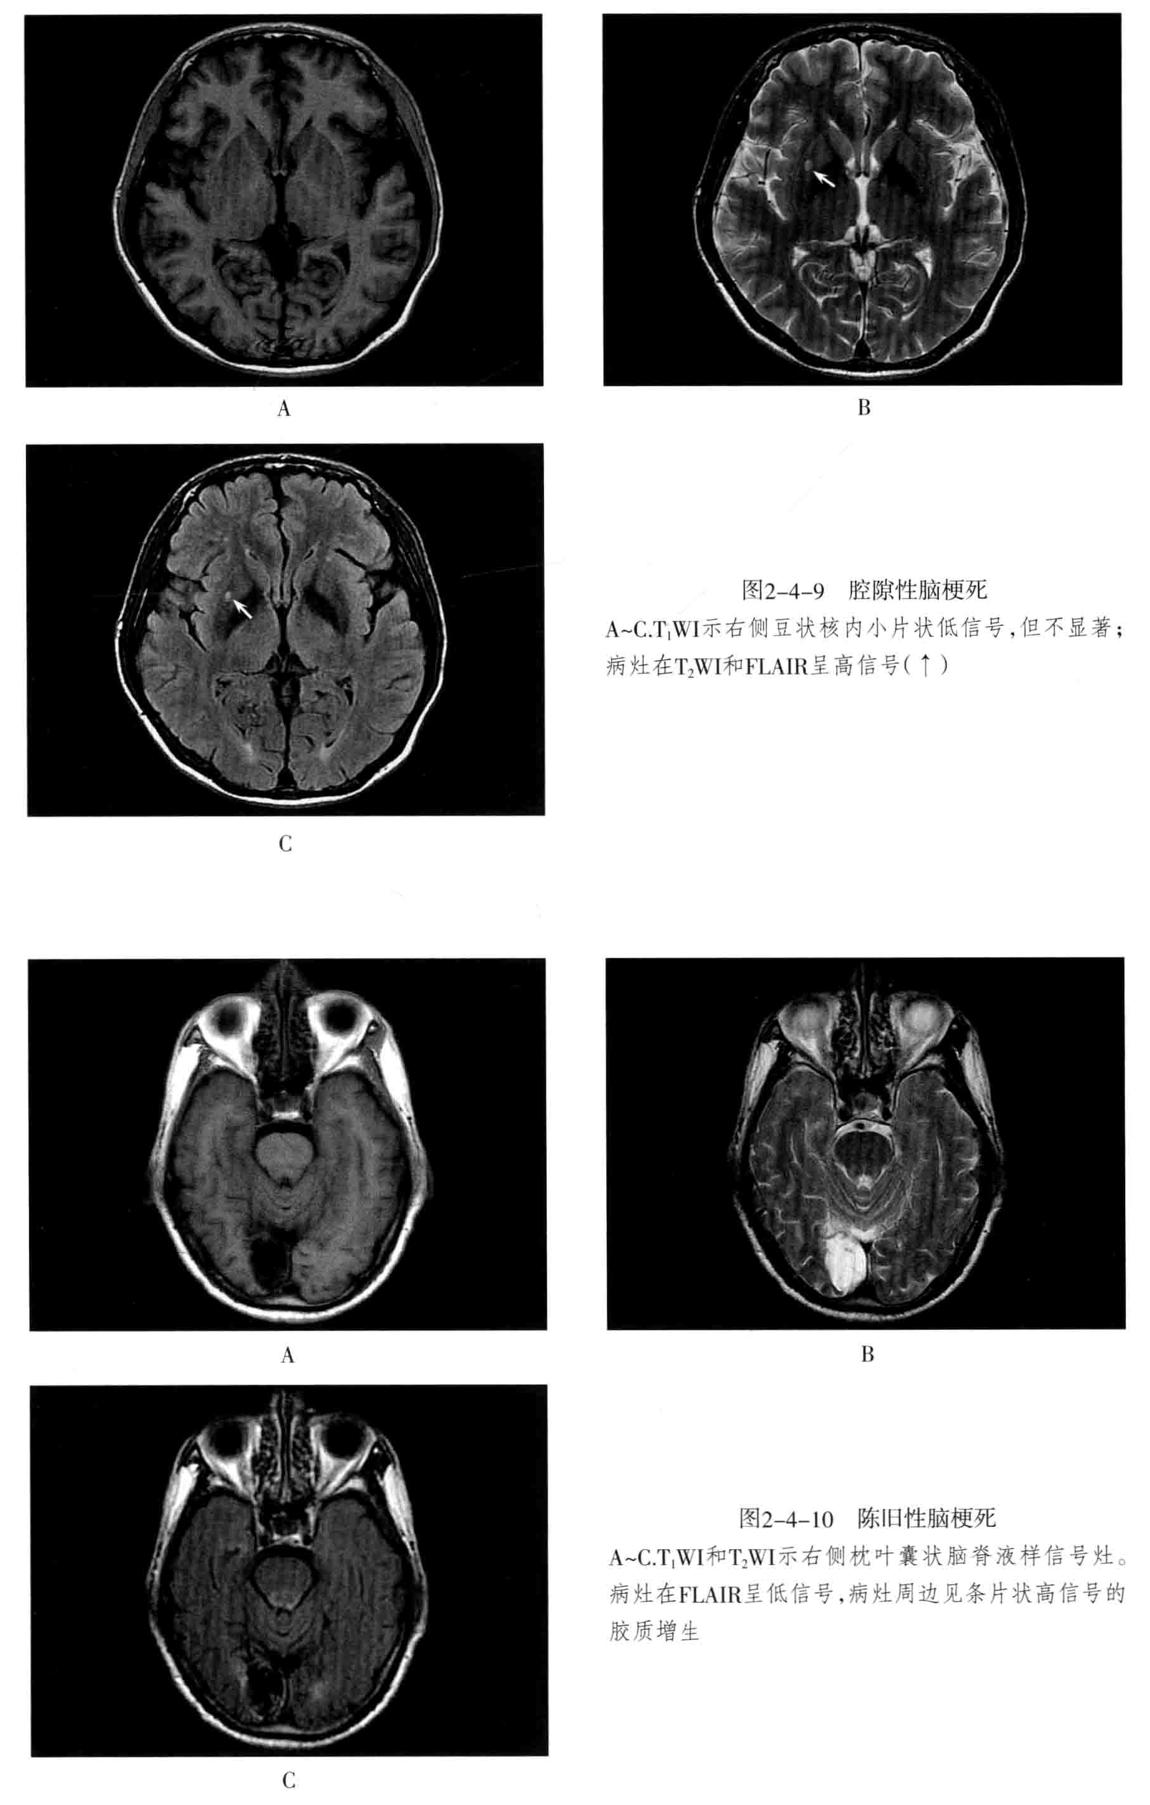

八、脑梗死:是一种缺血性脑血管疾病,常见有动脉闭塞性梗死和腔隙性脑梗死。主要病因为脑的大或中等管径的动脉发生粥样硬化,继发血栓形成,导致管腔狭窄、闭塞。以大脑中动脉闭塞最常见。脑梗死发生4-6小时脑组织发生缺血与水肿,继而脑组织出现坏死。1-2周后脑组织水肿逐渐减轻,坏死脑组织液化,梗死区出现吞噬细胞浸润,清除坏死组织,同时有胶质细胞增生和肉芽组织形成,8-10周后形成含液体的囊腔即软化灶。少数缺血性脑梗死在发病24-48小时后可因再灌注而发生梗死区内出血,转为出血性脑梗死。常见症状为偏瘫和偏侧感觉障碍、偏盲、失语等。

- CT表现为脑组织内低密度灶,梗死后2-15天为脑水肿高峰期,此时可有脑水肿表现;梗死1个月以后,相邻部位的脑室、脑池或脑沟扩大,出现脑萎缩表现。增强后梗死区可出现不均匀强化,呈脑回状、条状、环状或结节状强化。梗死区强化是由于血脑屏障破坏、新生毛细血管和血液灌注过度所致。

- MRI在脑梗死6小时之内,由于细胞毒性水肿,DWI可发现高信号,此后发生血管源性水肿、细胞死亡、髓鞘脱失、血脑屏障破坏,T1与T2弛豫时间延长。梗死后期,小的病灶不显示,表现为脑萎缩,大的病灶表现为软化灶。